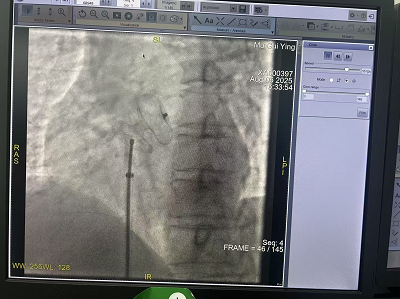

住院期间,我院心内科专家团队王思俊(副院长)、宇何健(内科二病区主任)、赵子凡(主任医师)在广元市第一人民医院心内科陈玺全主任指导下成功开展广元市县(区)域首例房间隔缺损(ASD)介入封堵术,标志着本地区先天性心脏病治疗迈入微创介入新时代。患者术后恢复良好,次日即可下床活动,3天后康复出院。

2.安全性高:全程在超声及X线引导下完成,精准定位,出血量不足10ml,显著降低感染风险。